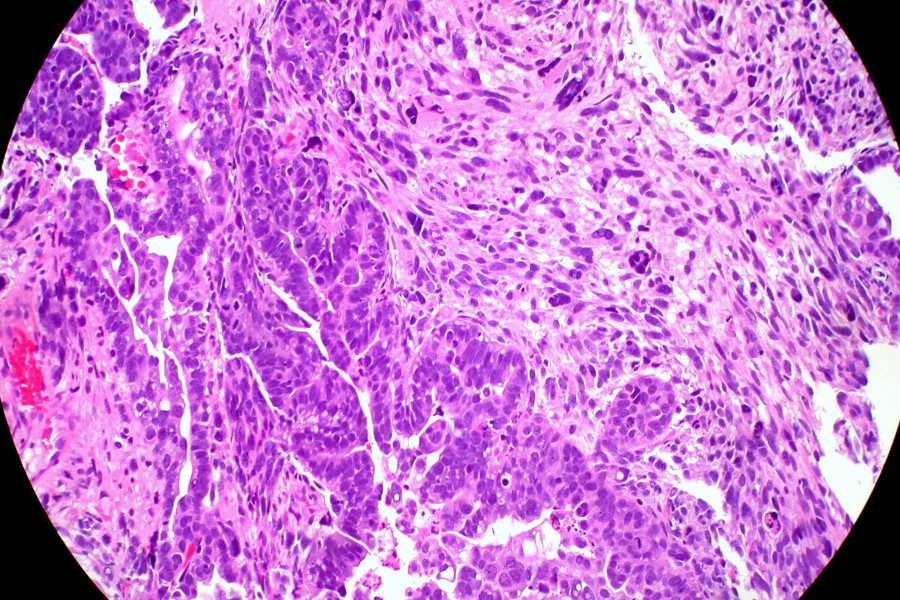

La inhibición de la proteína receptora CXCR6, asociada a una molécula conocida como CXCL16, podría ser clave para frenar la metástasis en pacientes con cáncer de endometrio. Esta afirmación surge de un estudio realizado por investigadores del Institut de Recerca Biomèdica de Lleida (IRBLleida) y la Universitat de Lleida (UdL), cuyos hallazgos han sido publicados en la revista Cell Death & Disease.

La citocina CXCL16 es parte del conjunto de sustancias que las células cancerosas liberan al entorno, lo que facilita el crecimiento tumoral, aumenta su capacidad invasiva y mejora su resistencia a los tratamientos. La elucidación de este mecanismo molecular no solo aporta información valiosa sobre el comportamiento del cáncer, sino que también abre la puerta al desarrollo de terapias más efectivas.

El equipo investigador ha utilizado modelos murinos y muestras de tejido humano para identificar este mecanismo molecular en células afectadas por la pérdida del gen ARID1A. Los resultados indican que inhibir la proteína CXCR6 o su receptor puede interrumpir las interacciones patogénicas, dificultando así la migración celular y reduciendo la carga metastática. Según Cristina Megino Luque, primera autora del artículo y actual investigadora en el Tisch Cancer Institute de Nueva York, esto sugiere una posible nueva estrategia terapéutica para aquellos pacientes con formas más avanzadas o agresivas de la enfermedad.